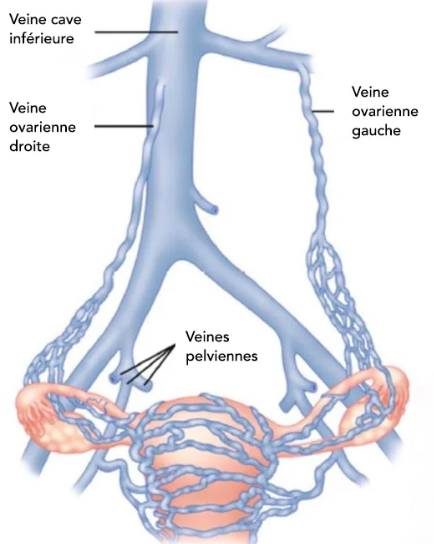

Anatomie

Anatomie